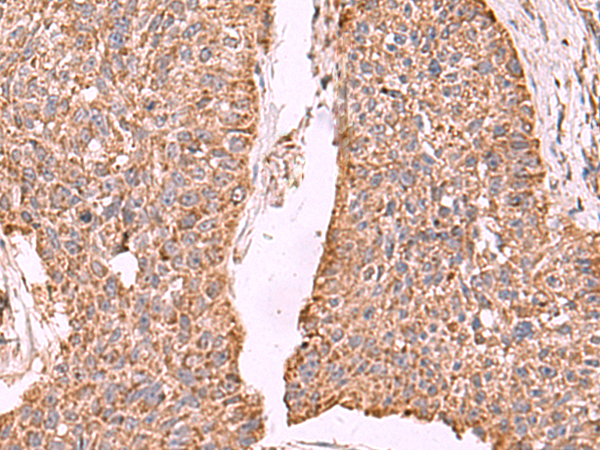

IHC positive control: |

Human esophagus cancer and Human cervical cancer |

IHC Recommend dilution: |

50-300 |